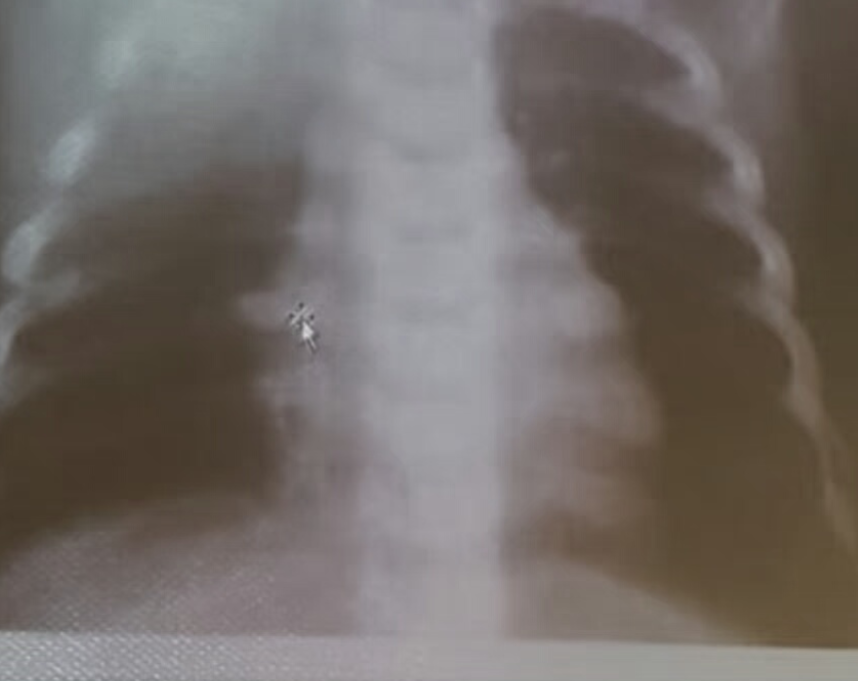

- AP chest film which shows complete opacification of the whole right lung - (1 .with shifted mediastinum and trachea to the left side

- .This indicates pleural effusion (PE) - (2

- After inserting chest tube, pus was coming out. This means that the PE is - (3 .an Empyema

- .The cause of this empyema is most likely a Bacterial Pneumonia - (4

- The age of the patient is 10 years which means that the most likely - (5 .organism is Streptococcus Pneumonae